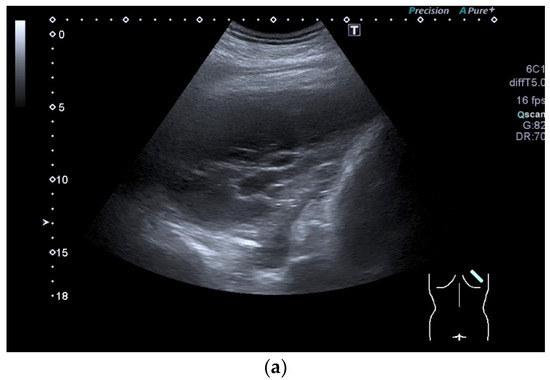

| Splenosis | Round, homogeneous lesions. Macrovessels on CDI are possible. Spleen-typical contrast behavior in CEUS with long-lasting contrast enhancement over several minutes. |

- Kroenig, J.; Zadeh, E.S.; Westhoff, C.C.; Klemmer, A.; Alhyari, A.; Görg, C. Diagnosis of Thoracic Splenosis by Contrast-Enhanced Ultrasound (CEUS). Ultraschall Med. 2022, 44, 645–646. [Google Scholar] [CrossRef]